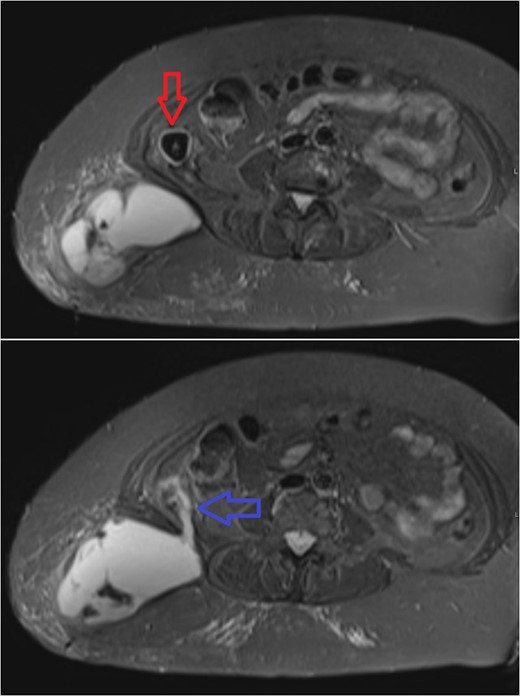

Subsequent axial MR sections of the pelvis. In the first image a large superficial collection can be seen in the soft tissues of the right lower back with surrounding fat stranding. A partially calcified, roughly spherical mass (3 cm in diameter) can be seen, walled-off within the abdominal cavity (red arrow). The second, more inferior section demonstrates communication (blue arrow) between the abscess cavity, through the belly of quadratus lumborum, and the calcified mass.

The study showed an abscess in the superficial tissues of the right lower back, communicating with a partially calcified mass in the right para-colic gutter. The presence of the mass as a likely infectious focus precluded percutaneous drainage and so the patient was referred to a general surgeon. She remained systemically well, and baseline investigations showed a normal white cell count, and only modestly elevated CRP levels at 53 mg dm−3. Abscess formation secondary to a dropped gallstone from her historical procedure was diagnosed, and she was listed for laparoscopic retrieval of the calculus with drainage of the abscess.